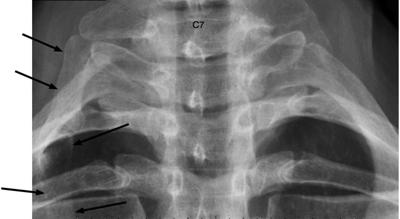

Lastly, a cervical rib can affect the arterial and nerve blood supply to the arm. This a patient currently under care here for symptoms simular to your husbands. But it's not common...